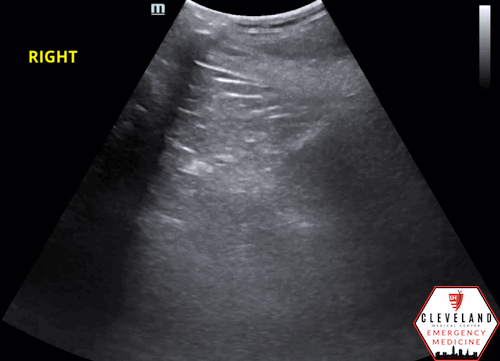

POCUS findings:

Dilated renal pelvis with multiple coalescing, anechoic calyces and parenchymal thinning, consistent with severe hydronephrosis bilaterally — new on the left, with more cortical thinning noted on the right. The bladder (not shown here) was fully decompressed.

**Both of this patient’s kidneys appear to have grade 4 or severe hydronephrosis based on ultrasound.